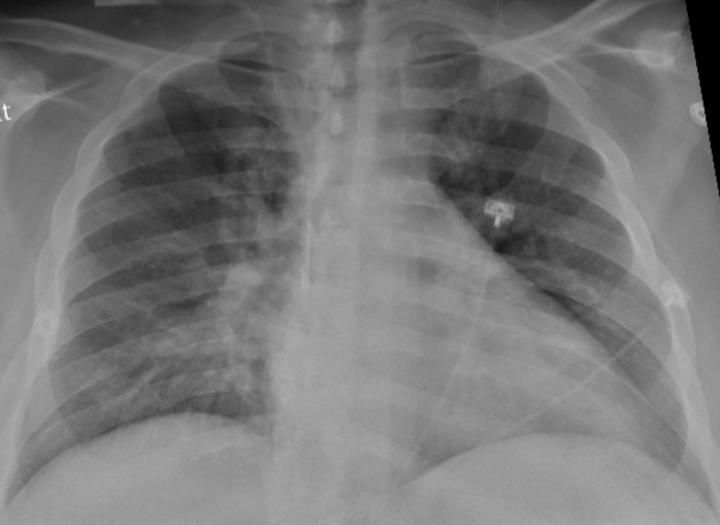

The virus that causes COVID-19 first attacks cells in the respiratory system, often leading to an inflammation of the lungs that puts people at risk of contracting pneumonia. But the virus' impact has also been felt in other systems of the body.